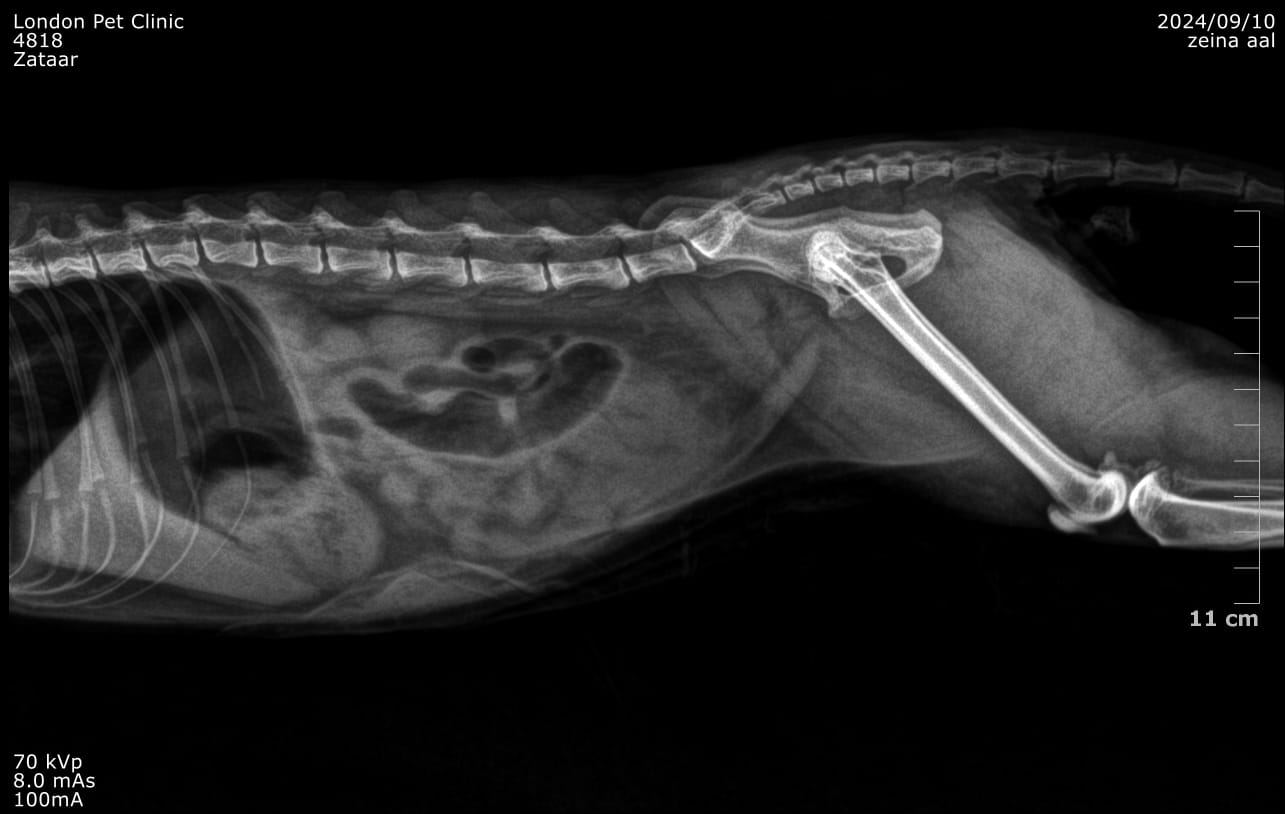

Abdominal radiographs: May show a gas--distended stomach with clogging clump

Abdominal ultrasound: was consistent of GOO due to hairball with fluid accumulation in the stomach

Post-Operative X ray